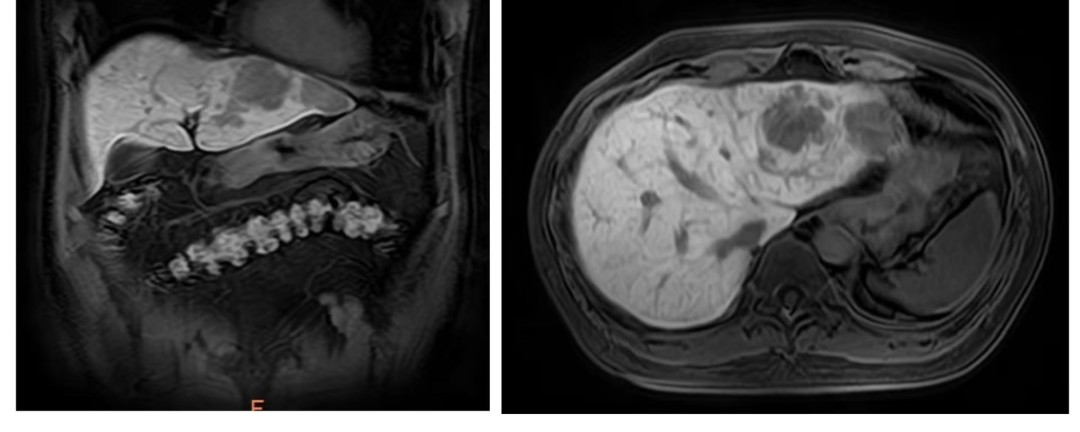

影像科为患者进行普美显造影的增强核磁共振,“肝脏病变的鉴别诊断就像破案,影像学证据是第一条线索。我们必须像‘侦察兵’一样,捕捉每一个微小细节。”影像科主任段庆红表示。专家们根据影像资料,逐一排查,不放过任何一个蛛丝马迹,最终一致认为张先生的肝脏病变具有良性特征,不具备典型快进快出的恶性肿瘤征象,高度符合肝血管瘤。

患者影像学报告